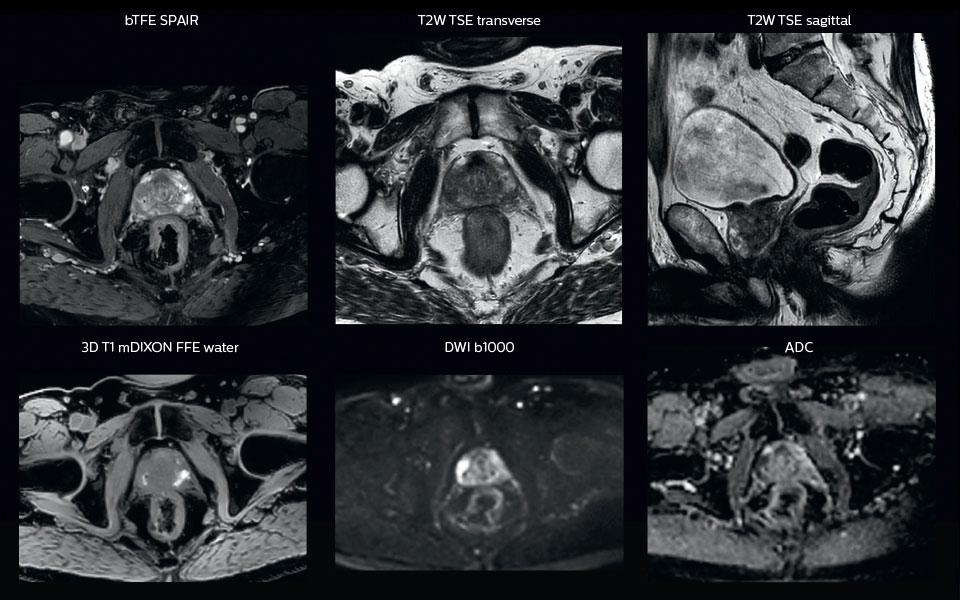

“All our patients undergo an MRI exam – along with CT – before radiotherapy of the prostate,” says Dr. Philippens. “For prostate delineation, we are scanning a balanced TFE with fat suppression. We can also see the gold fiducial markers in these images, which are used for position verification and are therefore used for registration to CT. For geometric accuracy of the image, we choose a 3D sequence, which is corrected for the gradient non-linearities in all directions.

“When we can visualize intraprostatic lesions, the radiation therapist can then plan to boost them, giving a higher dose to those lesions instead of giving a uniform dose to the whole prostate, in the hope to better treat the patient and have less risk of recurrent tumors. However, this is not yet clinical routine. For visualizing the lesions, we not only use anatomical, T2-weighted imaging, but also diffusion weighted MRI and dynamic contrast- enhanced MRI."

A 63-year-old patient with prostate cancer, cT3bNxM, Gleason 7, underwent MRI on Ingenia 3.0T MR-RT before radiation therapy.

Intraprostatic lesions are visible on the bTFE MR image, but not on the CT image. MRI shows excellent soft-tissue contrast for the visualization of critical structures like the rectum and penile bulb.

Fiducial markers (green arrows) are used in registration of MR images to CT, to transfer the MR-based delineations onto the CT image dataset.